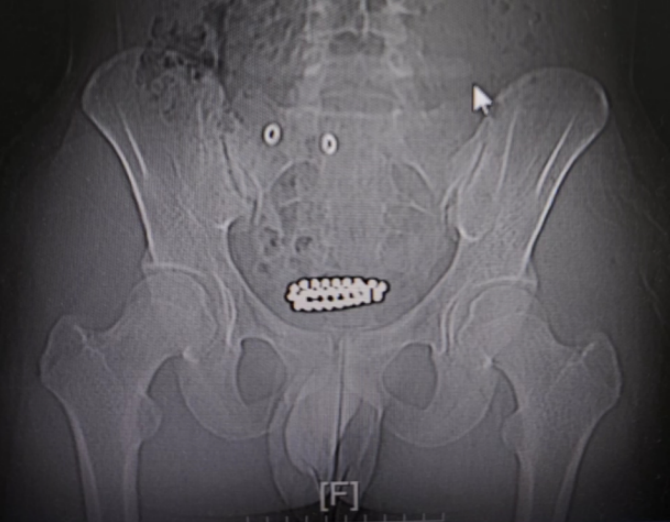

少年膀胱内惊现“磁手链”

近日,15岁的小华(化名)面色痛苦,双手紧捂下腹,因剧烈下腹痛、排尿困难、尿道口灼痛等症状,在家人陪伴下匆忙来到宁乡市中医医院就诊。

通过检查结果,医生看到了令人震惊的一幕——一圈“小珠子”静静地躺在孩子膀胱内,相互吸附、紧密嵌合,形成了一串完整的“手链”。诊断结果明确且危急,膀胱内多颗高强度磁性异物(磁力珠)。

在医生耐心的询问下小华道出了真相:他出于好奇,自行将几颗磁力珠塞入了尿道,顺着尿道进入的磁力珠无法取出。

祸已酿成,孩子慌了神,于是他继续往尿道塞珠子,希望用其他磁力珠的磁吸力能将塞进去的珠子牵引出来,哪里知道不但没有吸出来,被塞进去的珠子越走越深,最后逆行到达膀胱,形成了一串“手链”。